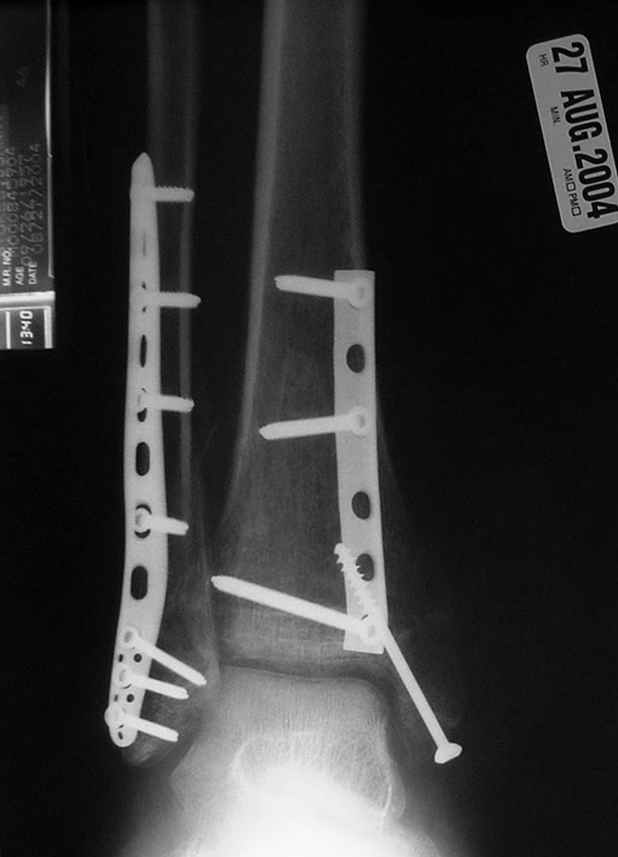

Отправитель: Djoldas Kuldjanov, M.D. 16 Сентябрь 2004, 22:00

Второй случай сделан из одного разреза

Дж

ЕЧ LISS plate, mininvasive approach - luxurous !

Вопрос практического характера - такой подход рутинный или при определенных показаниях и каких? Спрашиваю потому, что при потоке больных - закрытая голень, бедро, голеностоп и т.д. лучевая нагрузка должна быть немалая, каковы показатели дозиметра после такого операционного дня и при 2-3 операционных днях в неделю по 5-6 случаев (не считая ургентностей)?

С точки зрения : Сгорая сам - свети другим :-)) это вполне понятно, но личная практика показывает, что далеко не все пациенты относятся волнительно и критично к длине кожного разреза. Подозреваю, что это и есть критерий при выборе техники фиксации?

На прямой проекции послеоперационного Рг макроскопически все выглядит очень анатомично, при микроскопическом ( :-)) ) рассмотрении можно все-таки заметить вальгизацию тарана, суставная щель в латеральном отделе сустава несколько уже , чем в медиальном при отсутствии латерального смещения тарана. У меня был аналогичный случай (без LISS , без мини доступа) с вальгусным наклоном тарана при восстановленном ankle mortise при последовательном наблюдении с интервалами в 6-8 недель в послеоперационном периоде отмечалось прогрессирующее сужение суставной щели в латеральном отделе сустава, закончившееся посттравматическим ОА, к счастью боли умеренные, купируемые аналгетиками или своими эндорфинами:-))(активная пациентка, у которой нет времени на болезни....) Какова жизненная ситуация в приведенном вами случае? И последнее, что я хотел бы прояснить для себя - фиксация внутренней лодыжки: я обычно комбинирую фиксацию компрессирующим винтом со спицей - по идее ротационная стабильность должна быть лучше, чем один винт, каковы ваши наблюдения в этом плане?